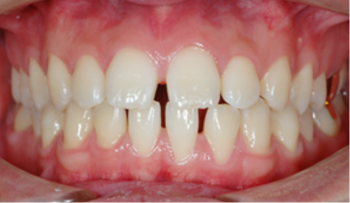

환자가 치료 계획에 동의하게 되면 수차례에 걸쳐 교정 장치가 부착되며

치료(유지)

교정 치료를 통해 개선된 치열 상태가 오랫동안 유지되도록